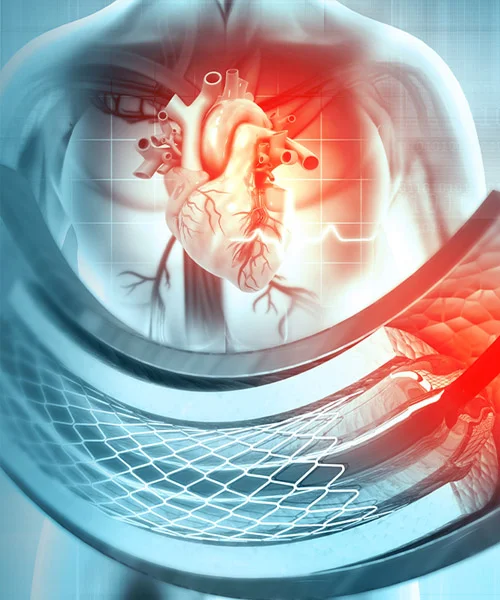

Advanced Cardiac Expertise

He holds prestigious qualifications including MBBS, MD in General Medicine, and DM in Cardiology, making him a highly skilled expert in interventional cardiology. Dr. Yogesh Nagendra has extensive expertise in procedures such as angiography, angioplasty, pacemaker implantation, Balloon Mitral Valvotomy (BMV), ECHO, and TMT, ensuring accurate diagnosis and effective treatment for every patient.